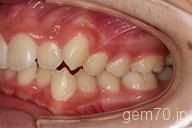

症状:叢生装置:セラミックブラケット | 非抜歯(歯を抜かない)世代:中学生

主訴)歯のでこぼこ

診断)叢生

年齢)14歳

使用装置)マルチブラケット装置

治療方法)非抜歯(歯を抜かない)

治療期間) 2年4ヵ月 通院回数 27回